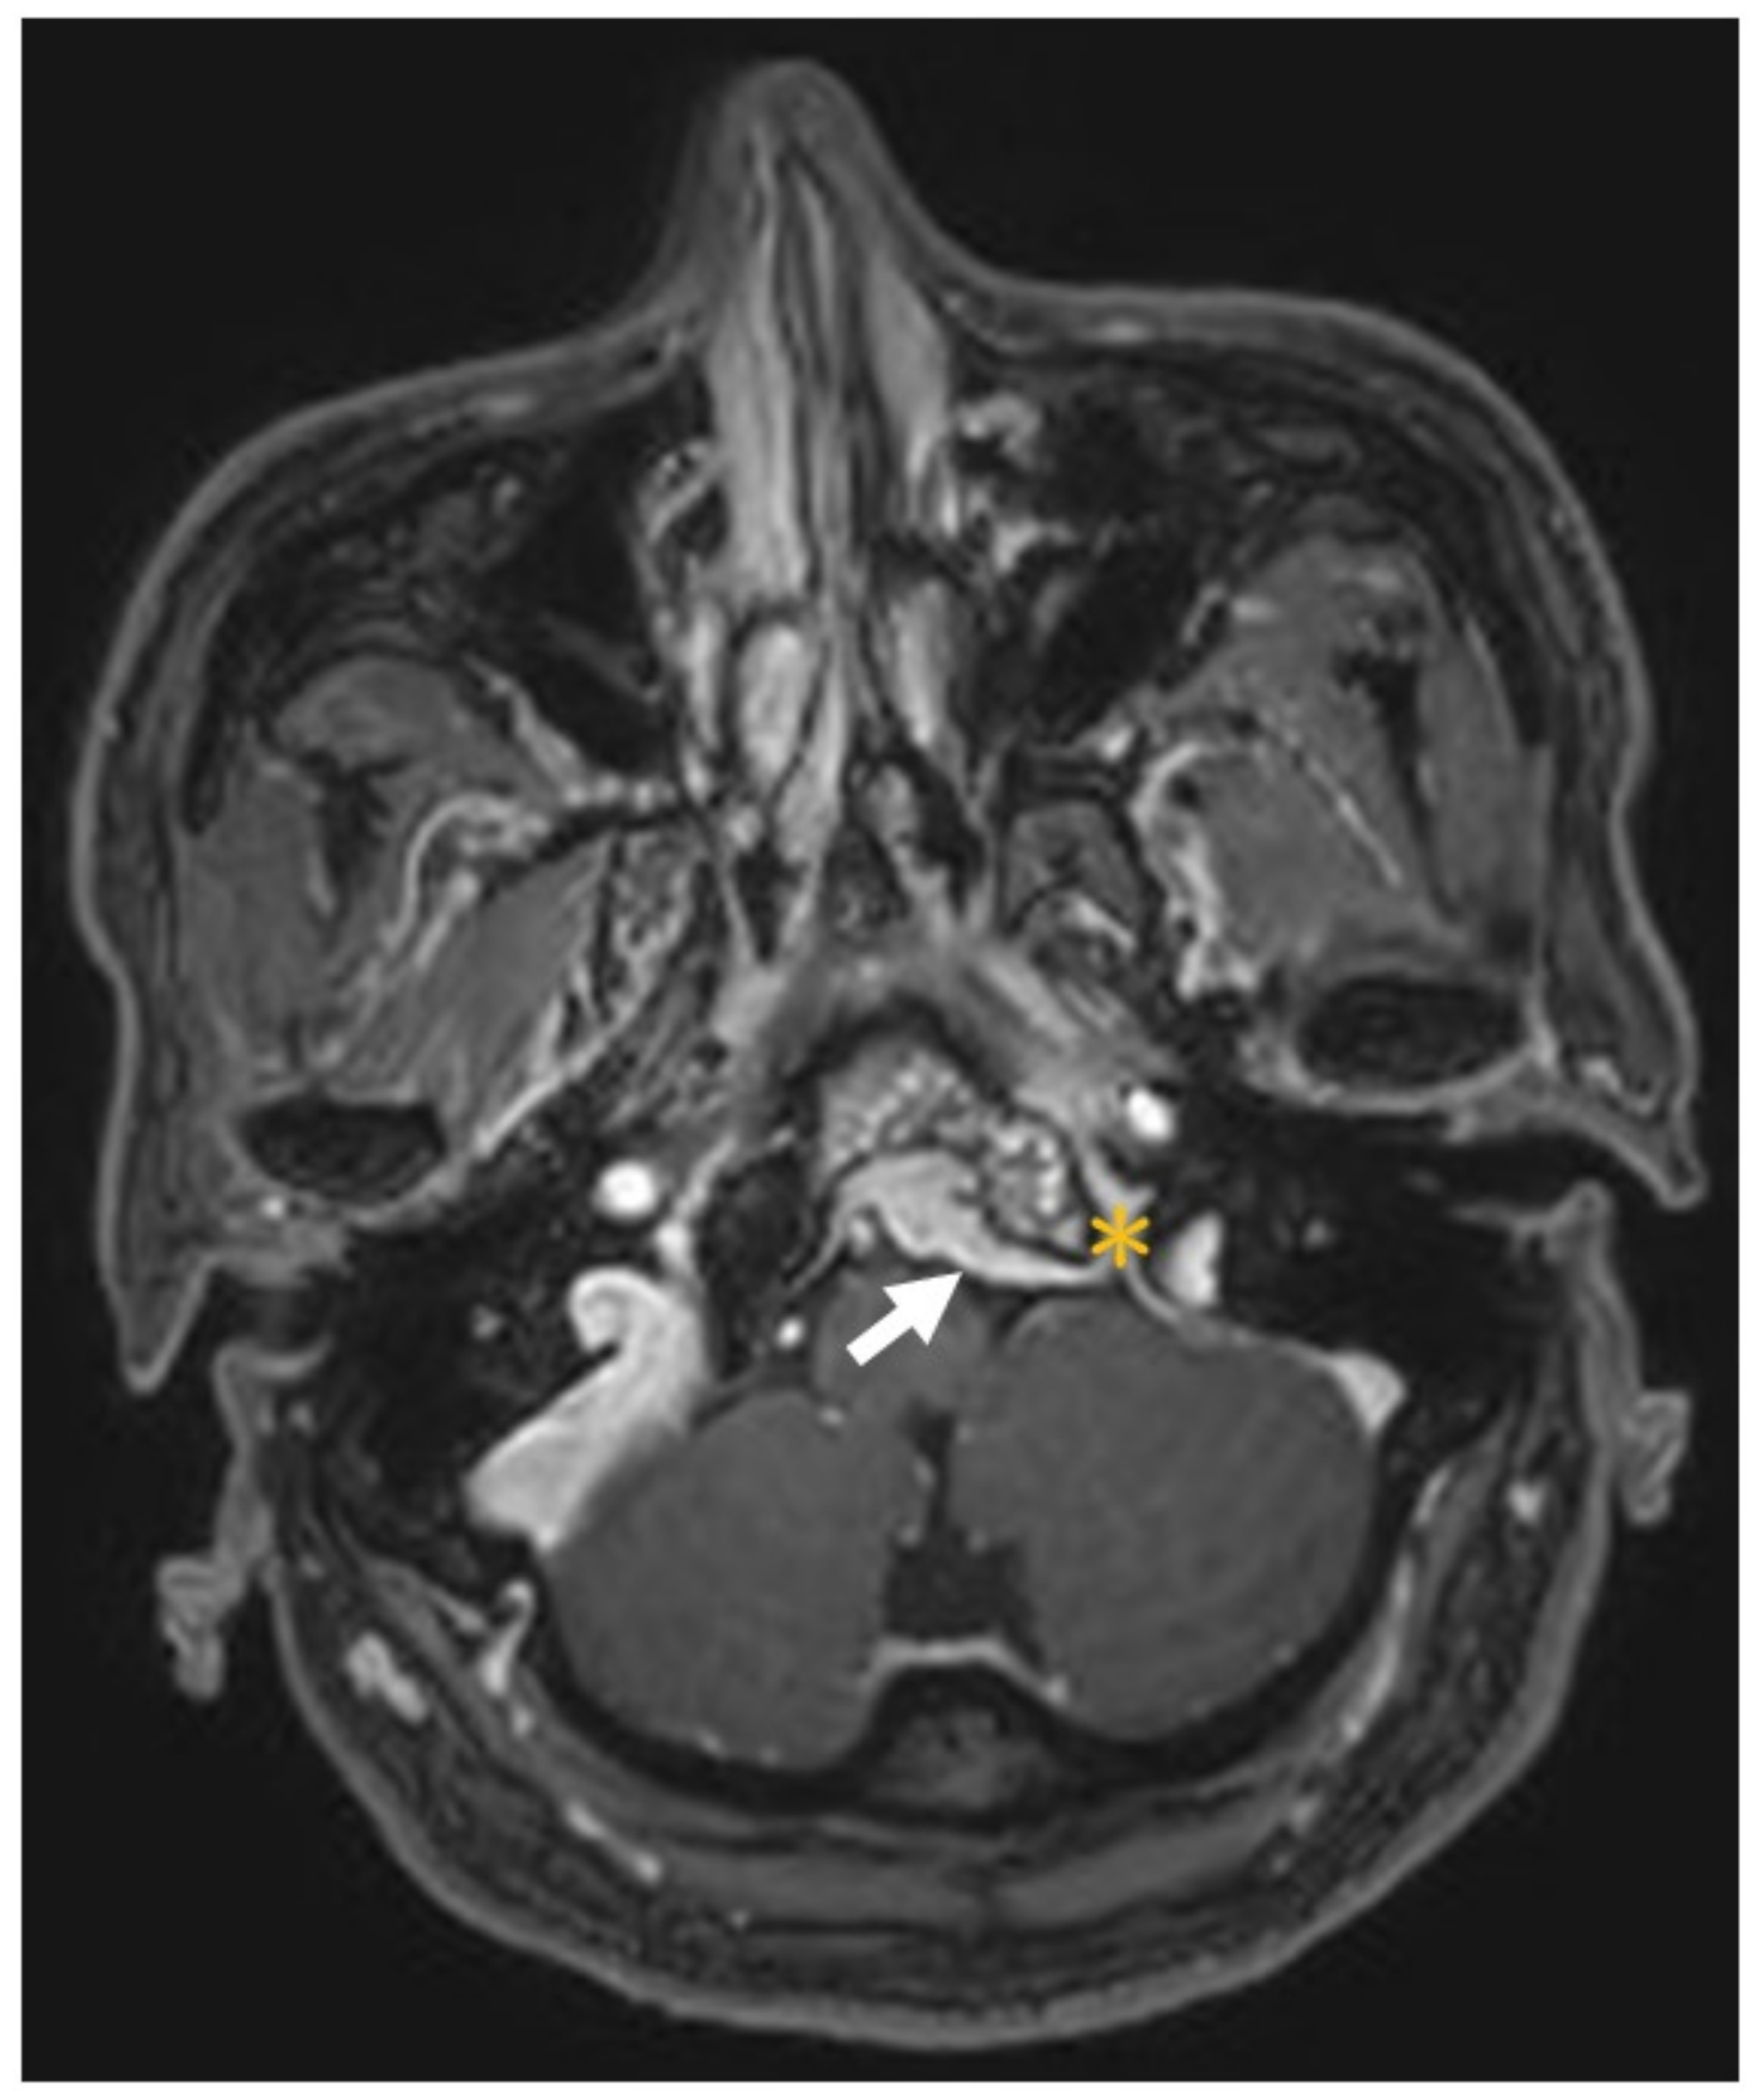

| Present case | Huang et al. | 48M | Dysphagia, hoarseness, tongue atrophy | JF, Clivus, HC, CA | IX, X, XII | T1 iso T2 hypo | + | nil | Endoscopic decompression surgery + prednisolone (10 mg/day for 100 days, oral) | 3 y |